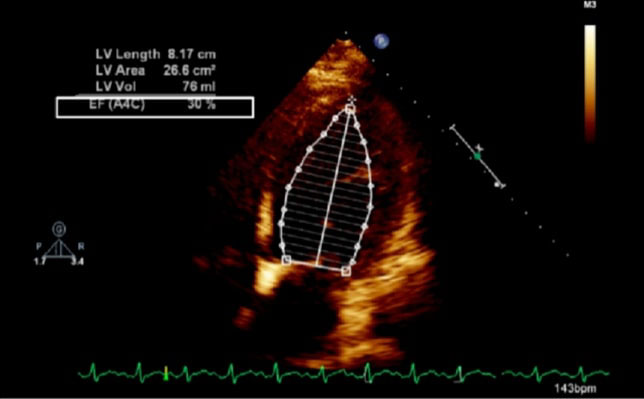

The exemption from the Institutional Review Board of Cleveland Clinic and consent from the patient were obtained for our case. A 42-year-old obese (body mass index 37.6 kg/m2) female at 38w2d, G2P1 with past medical history significant for gestational diabetes mellitus, presented with a three-day history of shortness of breath, orthopnea, chest tightness, tachycardia, headache, and swollen feet. She denied fever, vision changes, and right upper abdominal pain. No history of cardiac diseases or chronic hypertension was reported. Her vital signs included blood pressure (BP) of 145/98 mmHg, respiratory rate of 30 breaths per minute, heart rate of 150 beats per minute (bpm), and blood oxygen saturation (SpO2) of 98% on 10 liters per minute of oxygen through a non-rebreather mask. She was afebrile. Physical exam revealed loud S3 gallop, bilateral basilar rhonchi, and bilateral feet and ankle edema. Fetal monitoring was normal with a heart rate of 125 bpm. Laboratory results showed a white blood cell count of 12.8 k/µL, urine protein of 74 mg/dl, NT-proBNP of 1017 pg/ml, mildly elevated aspartate transaminase of 45 U/L and alanine transaminase of 30 U/L, and normal troponin. Electrocardiogram reported sinus tachycardia with borderline LV hypertrophy and frequent premature ventricular contractions (PVCs). Chest X-ray showed bilateral basilar infiltration. Echocardiogram revealed dilated LV with severely decreased function, EF of 25%, diffuse LV hypokinesia, and normal right ventricle function (Figure 1 and Figure 2). The patient started contractions and labor analgesia was administered through the epidural catheter; BP was noted to be 118/62 mmHg. Coagulation profile was normal. She was admitted to the intensive care unit (ICU) and Swan Ganz catheter, central, and arterial lines were inserted to monitor hemodynamics and heart function. Although our patient's clinical symptoms may lead us to consider preeclampsia, we ruled out preeclampsia because her labs did not meet criteria for diagnosis. Our patient was diagnosed with PPCM, for which she was placed on intravenous (IV) furosemide, tocolytic medication, and digoxin. Tocolytic medication was given to delay delivery until heart function improved, as the patient was unable to lie flat and EF was very low.

Figure 1: Echocardiogram of apical four chamber view of the heart showing dilated left ventricle and reduced ejection fraction; LV: left ventricle, EF: ejection fraction, A4C: apical four chamber, Vol: volume.